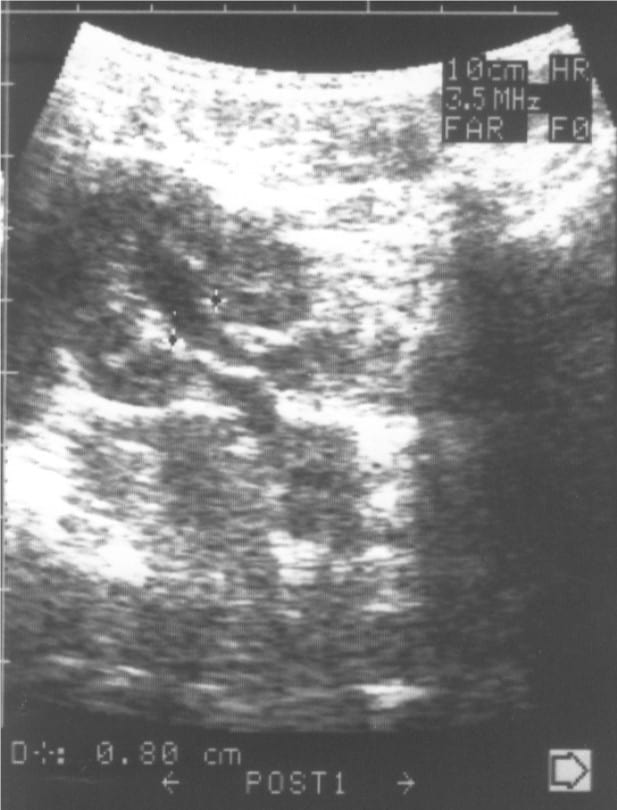

Фиг. 2. а/ – Пиелектазия – незначително отслояване на стените на бъбречното легенче, надлъжен срез и б/ Пиелектазия – напречен разрез на легенчето с предно-заден размер на дилатацията до 5 мм.

Специално прилагам УЗ образ /Фиг.2/ на това установено в УЗ образ на бъбреците при кърмачета отклонение, защото то е често срещано, но много рядко налага допълнителни изследвания.

И когато от всичките посочени петнадесет УЗ параметъра отклонение има само в един /малко количество урина в пиелона – пиелектазия/ при здраво кърмаче без данни за уроинфекция, изпратено на профилактичен преглед, НЯМА ПОКАЗАНИЯ ЗА ПРОВЕЖДАНЕ НА ДОПЪЛНИТЕЛНИ ИЗСЛЕДВАНИЯ – МИКЦИОННА ЦИСТОГРАФИЯ „ЗА ДА ВИДИМ ДАЛИ НЕ СЕ ВРЪЩА УРИНА„.

Особено внимание ще отделя това най-често „малко” отклонение с наличие на незначително количество урина в пиелона – пиелектазия /Фиг.2/.